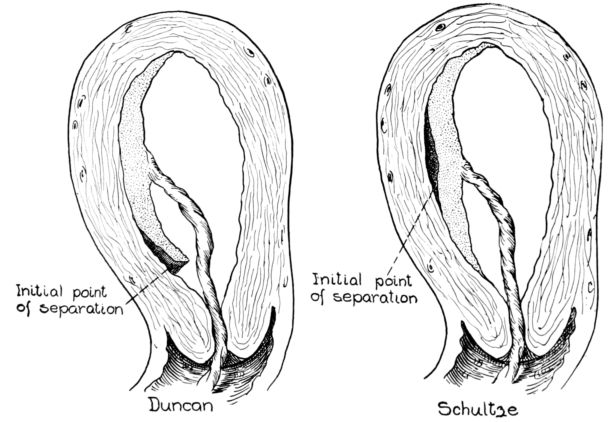

| 71. | Diagrams of Duncan and Schultze mechanisms of placental separation | 239 |